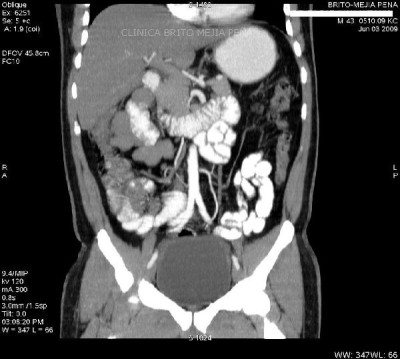

Pseudoquiste páncreas coronal